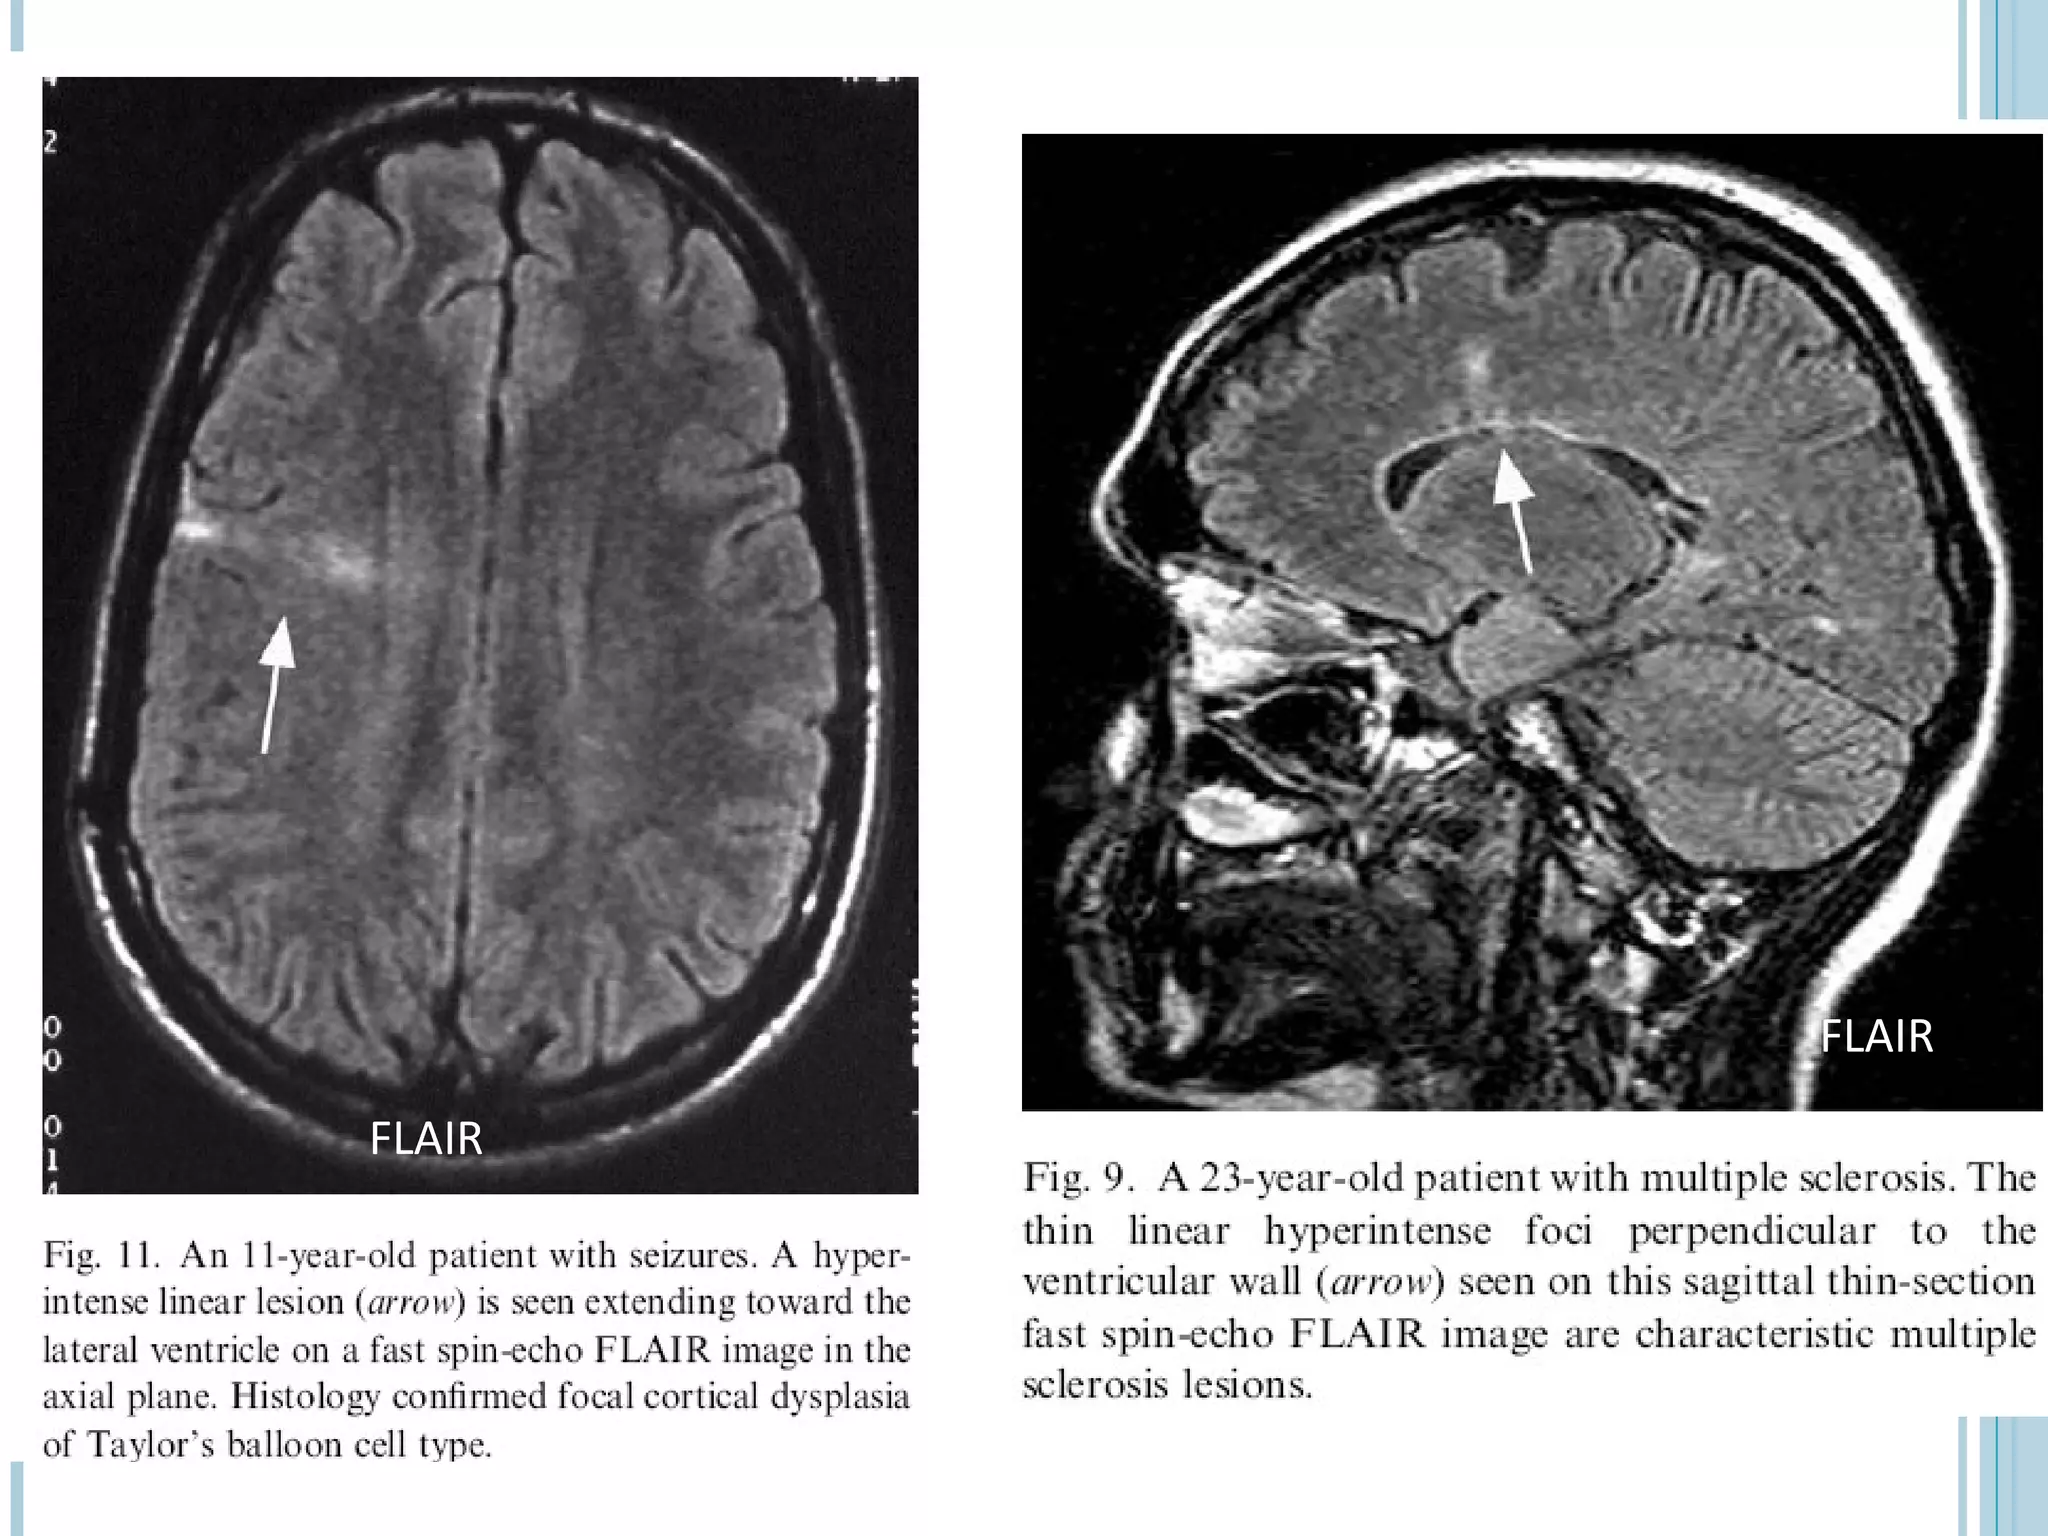

   Focal cortical dysplasia of Taylor’s balloon cell type- markedly hyperintense funnel-

shaped subcortical zone tapering toward the lateral ventricle is the characteristic

FLAIR imaging finding

   Embolic infarcts- Improved visualization

Mesial temporal sclerosis: m/c pathology in patients with partial complex seizures.Thin-section coronal FLAIR is the standard sequence in these patients & seen as a bright small hippocampus on dark background of suppressed CSF- containing spaces. However, normally also mesial temporal lobes have mildly increased SI on FLAIR images.  Focal cortical dysplasia of Taylor’s balloon cell type- markedly hyperintense funnel- shaped subcortical zone tapering toward the lateral ventricle is the characteristic FLAIR imaging finding  In tuberous sclerosis- detection of hamartomatous lesions, is easier with FLAIR than with PD or T2-W sequences

Embolic infarcts- Improved visualization  Chronic infarctions- typically dark with a rim of high signal. Bright peripheral zone corresponds to gliosis, which is well seen on FLAIR and may be used to distinguish old lacunar infarcts from dilated perivascular spaces.